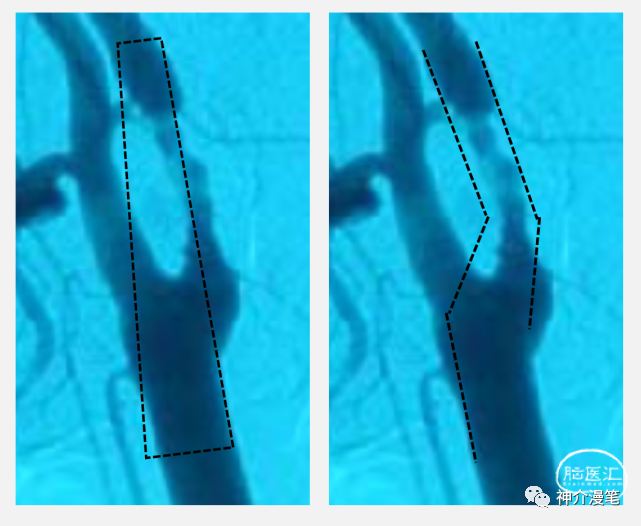

对于血管走形迂曲,管径差异较大,偏心性狭窄。预期支架贴壁困难时,首选开环支架。因为其独立支架单元的结构,更容易贴壁。下图所示,管径差异较大时,左图的闭环支架在狭窄局部贴壁不良,而右图的开环则有更好的贴壁性。

从其他角度讲,开环支架对于血管走形的改变会较小,能大体顺应血管走行。而闭环支架更多的趋势是趋于一根直棒棒,对于迂曲血管走行相对改变较大。其实很多情况下,我们并不希望血管的走行被改变过大。下图为闭环和开环释放后对血管走行改变的模式图,左图为闭环释放后血管的形态预测,整体的走行改变还是会大一些。